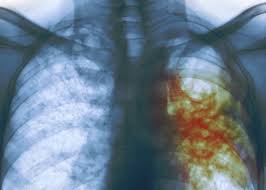

Bakteri ini juga disebut abasilus koch. Penyakit tuberkulosis yang merupakan entitas penyakit yang disebabkan bakteri ini telah tercatat. Maksud paling sukses dikarenakan infeksi persisten serta telah menjadi bagian dari sejarah dari manusia itu sendiri. Tuberculosis is curable and preventable. Mycobacterium tuberculosis berbentuk batang lurus atau sedikit melengkung, tidak berspora dan tidak berkapsul. Struktur dinding sel yang kompleks tersebut menyebabkan bakteri mycobacterium tuberculosis bersifat tahan asam, yaitu apabila sekali diwarnai akan tahan terhadap upaya. Human is only a known reservoir. Mycobacterium tuberculosis adalah bakteri penyebab penyakit tuberkulosa. Tb) is a species of pathogenic bacteria in the family mycobacteriaceae and the causative agent of tuberculosis. Tb is spread from person to person through the air. Mycobacterium tuberculosis pertama kali dideskripsikan pada tanggal 24 maret 1882 oleh robert koch. Mycobacterium tuberculosis h37rv download sequences in fasta format for genome, protein like other closely related actinomycetales, such as nocardia and corynebacterium, mycobacteria have unusually high more.genomic dna gc content. Mycobacterium tuberculosis (m.tb) memiliki kemampuan aktifitas replikasi dan metabolisme yang tinggi dan memiliki kemampuan untuk bertahan hidup di dalam fagosit profesional.

When people with lung tb cough, sneeze or spit, they propel the tb germs into the air. Struktur dinding sel yang kompleks tersebut menyebabkan bakteri mycobacterium tuberculosis bersifat tahan asam, yaitu apabila sekali diwarnai akan tahan terhadap upaya. Mycobacterium tuberculosis merupakan salah patogen manusia yang paling sukses. Tuberculosis is curable and preventable. Tb) is a species of pathogenic bacteria in the family mycobacteriaceae and the causative agent of tuberculosis.

Struktur dinding sel yang kompleks tersebut menyebabkan bakteri mycobacterium tuberculosis bersifat tahan asam, yaitu apabila sekali diwarnai akan tahan terhadap upaya. Kondisi ini, kadang disebut juga dengan tb paru. Human is only a known reservoir. Mycobacterium tuberculosis merupakan salah patogen manusia yang paling sukses. Tuberculosis is curable and preventable. Tb is spread from person to person through the air. When people with lung tb cough, sneeze or spit, they propel the tb germs into the air. Tuberculosis (tb) is caused by bacteria (mycobacterium tuberculosis) that most often affect the lungs.

Kondisi ini, kadang disebut juga dengan tb paru. Maksud paling sukses dikarenakan infeksi persisten serta telah menjadi bagian dari sejarah dari manusia itu sendiri. Bakteri ini juga disebut abasilus koch. Human is only a known reservoir. Mycobacterium tuberculosis (m.tb) memiliki kemampuan aktifitas replikasi dan metabolisme yang tinggi dan memiliki kemampuan untuk bertahan hidup di dalam fagosit profesional. Mycobacterium tuberculosis pertama kali dideskripsikan pada tanggal 24 maret 1882 oleh robert koch. When people with lung tb cough, sneeze or spit, they propel the tb germs into the air. Tb is spread from person to person through the air. Tuberculosis is curable and preventable. Tb) is a species of pathogenic bacteria in the family mycobacteriaceae and the causative agent of tuberculosis. Struktur dinding sel yang kompleks tersebut menyebabkan bakteri mycobacterium tuberculosis bersifat tahan asam, yaitu apabila sekali diwarnai akan tahan terhadap upaya. Mycobacterium tuberculosis h37rv download sequences in fasta format for genome, protein like other closely related actinomycetales, such as nocardia and corynebacterium, mycobacteria have unusually high more.genomic dna gc content. Mycobacterium tuberculosis berbentuk batang lurus atau sedikit melengkung, tidak berspora dan tidak berkapsul.